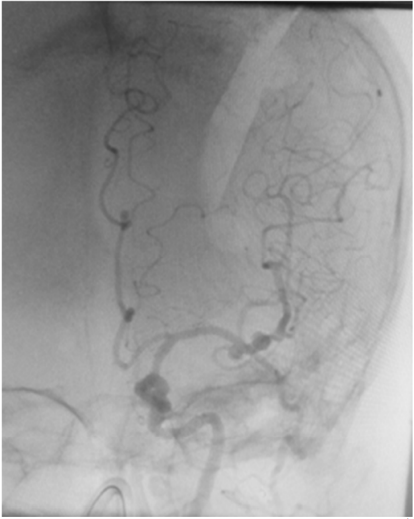

Uma paciente de 66 anos de idade, tabagista, hipertensa com tratamento irregular. Apresentou cefaleia súbita de severa intensidade associada a náuseas. Ao exame físico, observaramse AC = RR2T com BNF, FC = 100 bpm, AP = MVF sem RA, FR = 15 irpm, PA = 182 mmHg x 100 mmHg, SatO2 em ar ambiente = 97%, Glasgow 15, pupilas isofotorreagentes, sem deficits focais. TC crânio e arteriografia a seguir.

Fonte: Acervo pessoal.